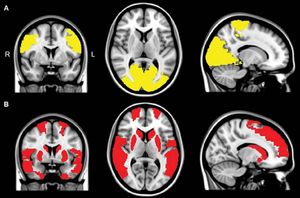

Gehirn-Scans: Parkinson verändert die Kommunikation im Kopf (Foto: rsna.org) |

Den Forschern nach kommunizierten bei Parkinson-Patienten im Vergleich zur Kontrollgruppe mehrere Gehirnbereiche weniger mit dem Rest des Gehirns. Bei Patienten mit visuellen Halluzinationen wiesen mehrere zusätzliche Gehirnbereiche diese verringerte Konnektivität auf. Betroffen waren vor allem jene, die wichtig für das Aufrechterhalten der Aufmerksamkeit und die Verarbeitung von visuellen Informationen sind. Sie waren laut Studienautor Menno M. Schoonheim weniger mit dem restlichen Gehirn verbunden. Damit liege nahe, dass die Unterbrechung dieser Verbindungen beim Entstehen von visuellen Halluzinationen eine Rolle spielen. Die Forschungsergebnisse wurden im Fachmagazin "Radiology" veröffentlicht.